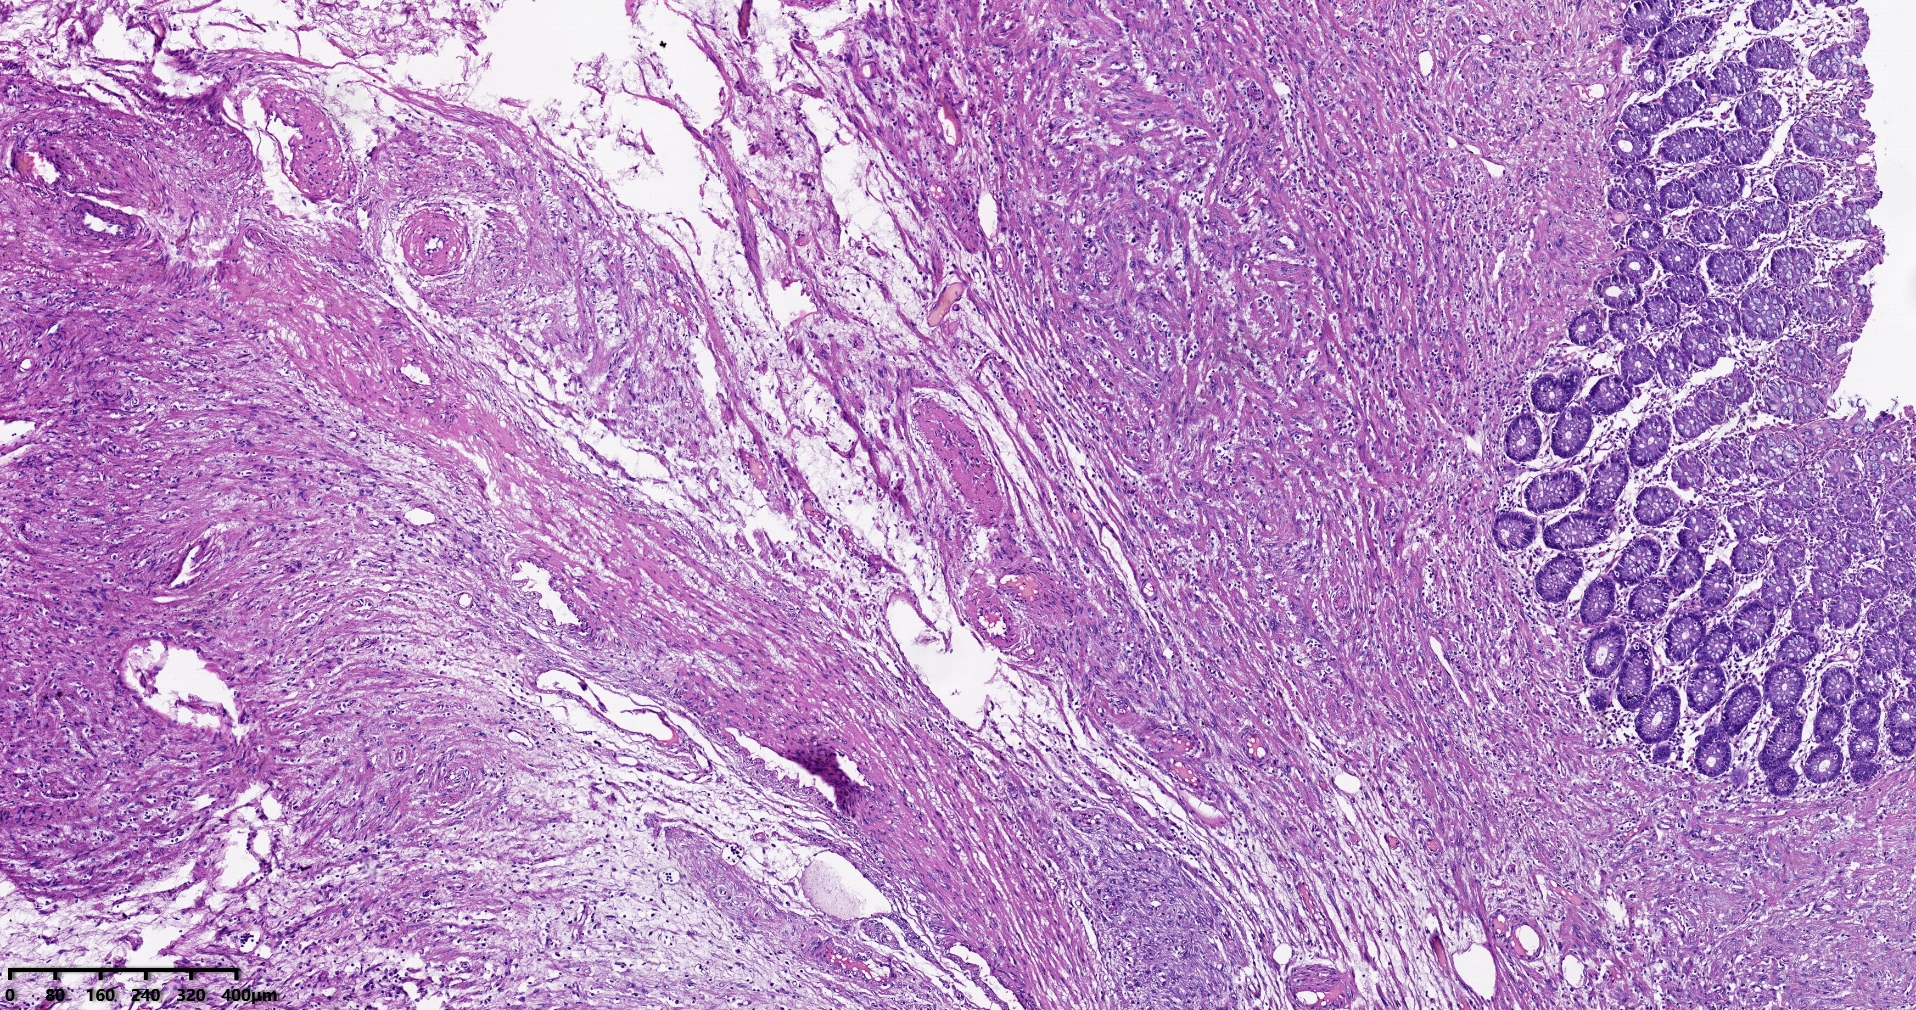

结肠肝曲息肉状肿物,平滑肌瘤?胃肠道间质瘤?炎性纤维性息肉?

性别

男

年龄

56岁

临床诊断

结肠肝曲息肉

一般病史

不详

标本名称

大体所见

灰红色椭圆形息肉一个,直径2.5cm,蒂长0.5cm,切面灰白灰红色,质中。

请路过的老师指教。

图1

考虑间质瘤?

就HE形态而言,间质瘤的可能性要大一些,建议做免疫组化协助鉴别。